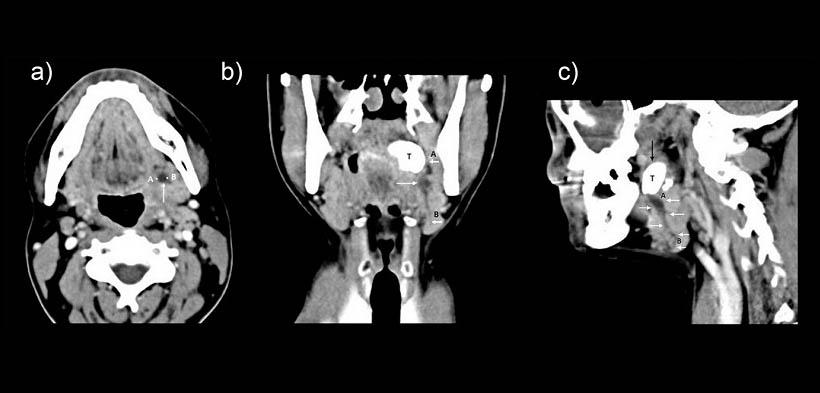

Fig. 4. (a) TC, vista axial que muestra una imagen hipodensa correspondiente al trayecto fistuloso de la parte izquierda (flecha blanca), comenzando en el polo inferior de la amígdala, que mide 6 mm de ancho (A-B). (b, c) vista coronal y sagital que muestran la masa calcificada (tonsilolito, flecha oscura), a nivel de la región periamigdalino izquierda con un trayecto fistuloso hipodensa (flechas blancas) que se extiende desde el polo amigdalar inferior (A) hacia la glándula submandibular izquierda (B), la medición del trayecto fistulosos es de 36 mm de longitud (A-B).